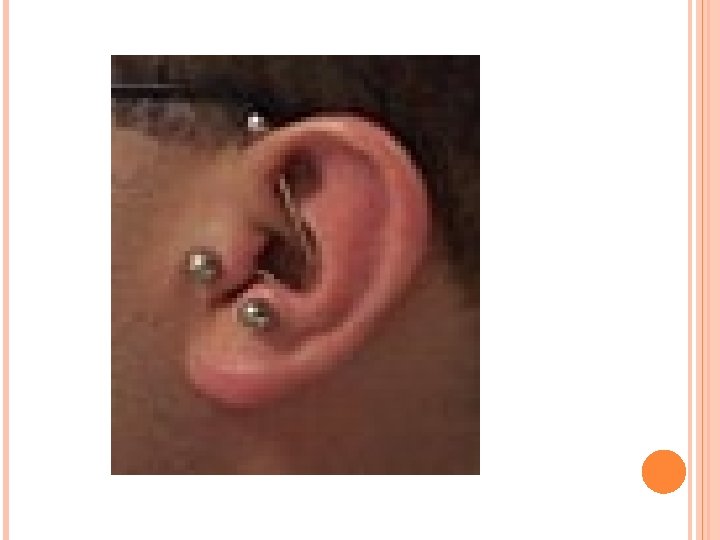

Tratamiento Eliminar el material infectado que se encuentra en el canal mediante aspiración o con hisopos. Instilacion de gotas de antibiótico. Analgésicos como la codeína. Antibiótico via oral. Se deja que los furúnculos drenen por sí solos porque el hecho de abrirlos puede diseminar la infección. Pericondritis del pabellón auricular Es la inflamación del pericondrio que recubre el cartílago del pabellón auricular, suele estar producidad por Pseudomona aeruginosa. Por traumático, otohematona, cirugía, picadura de insecto. Pericondritis por erisipela es una enfermedad post streptococcica (Streptococo b hemolítico). Oreja aparece enrojecida, tumefacta y dolorosa. Si la infección progresa hay necrosis del cartílago. Tratamiento Consiste en la evacuación de la colección purulenta , vendaje compresivo y antibióticos.

Quiste sebaceo Los quistes sebáceos son acumulaciones protuberantes, en forma de saco, de células cutáneas muertas y aceites producidos por las glándulas sebáceas en la piel. La causa exacta se desconoce, pero los quistes pueden aparecer cuando la producción de aceites en una glándula cutánea es más rápida que su excreción de dicha glándula. Síntomas Dolor (si los quistes están en el conducto auditivo externo o se infectan). Tratamiento Si un quiste se vuelve doloroso, es posible que esté infectado. El tratamiento puede incluir antibióticos o extirpación del mismo.